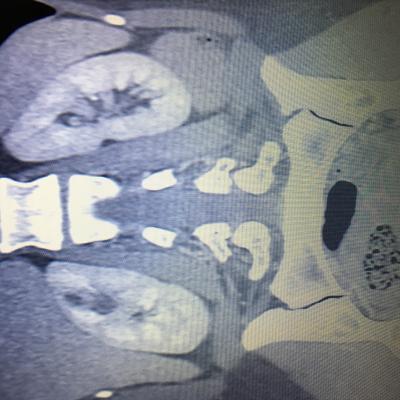

Здравствуйте,помогите, пожалуйста, с расшифровкой кт почек с контрастом. Насколько я поняла, в левой почке маленький камешек. А что за образование в правой почке? Киста с кальцинированной стенкой или камень? Спасибо за ответ!

Здравствуйте! На последнем снимке - больше данных за конкремент. Но при описании снимков должны определяться плотность образования, и нет изображения ни одного фрагмента ни одного из мочеточников. И самих снимков обычно бывает больше. Недостаточно данных для заключения.